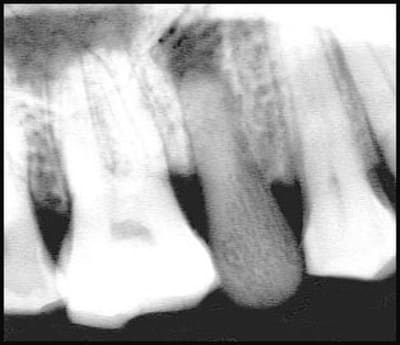

identifier cette radio

qu'est ce que cette dent PM?

question un peu plus difficile, à qui appartient cette dent?

Je pense que ce n'est pas une dent.

Je penche pour de l'ivoire.

J'ai du mal à expliquer le granulome.

curieux les trabéculations.

d'accord avec Alapex, et posit qui a posté pendant que je rédigeais

radio post mortem

Pm en os ou ivoire ?

Décédé peu de temps apres l'extraction et la pose de l'implant : pas de cicatrisation osseuse, ni granulome autour de tout l'implant.

Age 25-30ans, certainement fortuné, certainement un homme ? Alimentation cereales et légumineuses , malgré l'absence de carie? Peutetre du sable dans l'environnement ?